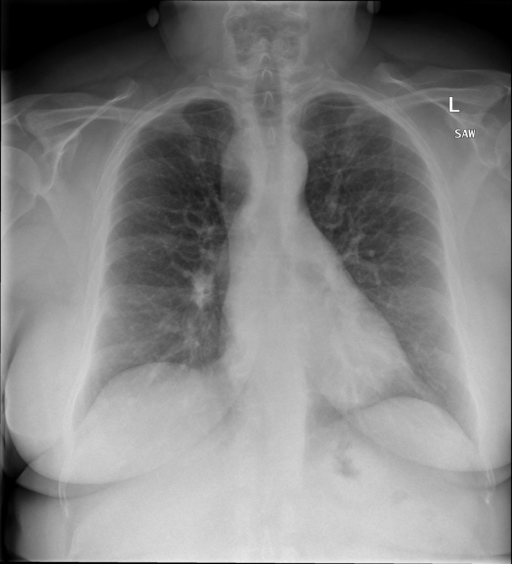

多轮对话:

|X光影像|诊疗报告(医生)|

|:-|:-|

||右侧主动脉突出观察到。心脏大小正常。胸部未发现明显的肺气肿、胸膜积液或可疑的肺部病变。报告指出已知右侧主动脉情况正常。|

```bash

>> X光影像路径:./data/Xray/861_1.png

>> 用户:这是一张什么图?

>> XrayGLM:这张图片显示的是一张肺部检查的X光片。

>> 用户:请描述这张胸部X光片的诊断结果

>> XrayGLM:心脏大小正常,肺部清晰。没有急性心肺疾病的证据。

>> 用户:是否存在肺气肿?

>> XrayGLM:没有肺气肿。心脏大小正常,肺部清晰。没有发现急性心肺疾病的证据。

>> 用户:平时饮食该注意什么?

>> XrayGLM:饮食应该健康,均衡。建议增加蛋白质的摄入量,因为蛋白质有助于维持肌肉和骨骼的健康。多食用蔬菜、水果、全谷物以及健康的脂肪来源如橄榄油、鱼类等可以帮助获得足够的维生素和矿物质。此外,避免过度饮酒或吸烟,这些习惯可能会对心脏健康产生负面影响。

```